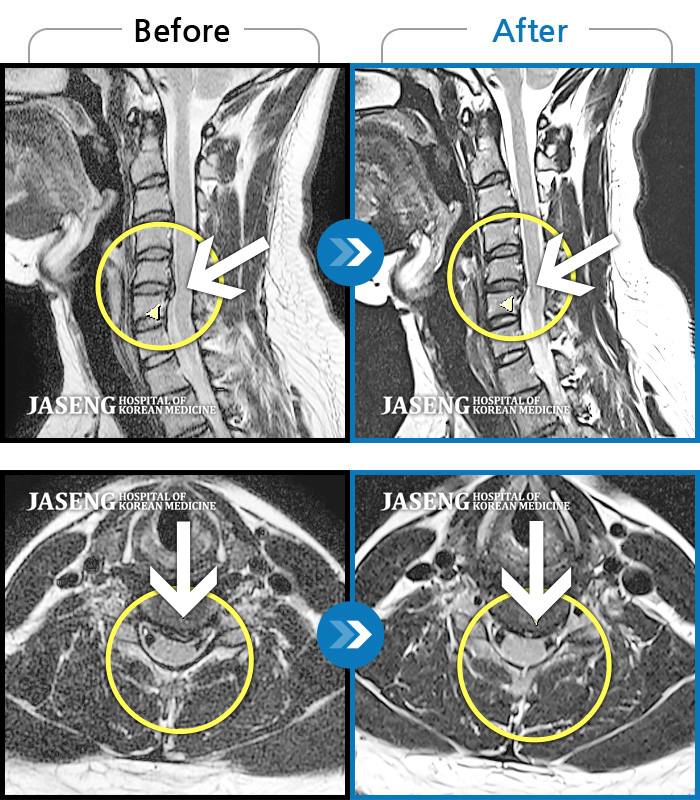

목디스크

광주 · 장영우 원장

후경부 양측부터 승모근까지 묵직한 통증, 좌측 상지 수지까지 이어지는 저린감

촬영시기

2121.04.27 ~ 2121.12.11